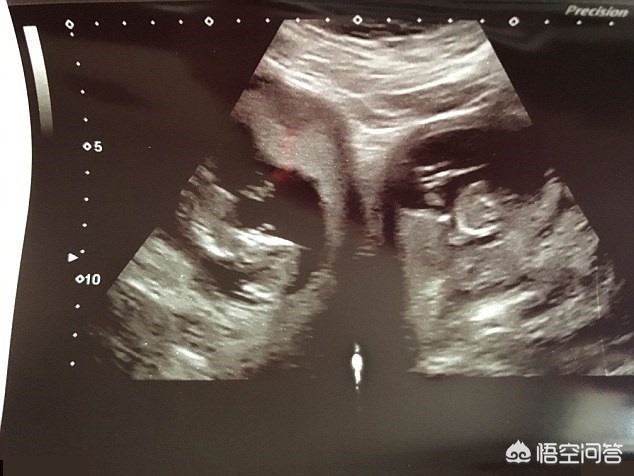

双子宫

双胞胎

还是龙凤胎

双子宫怀上龙凤双胞胎

到了2月份,医生在进一步的检查中发现,詹妮弗居然是双子宫,一对双胞胎个占据其中的一个宫腔。

詹妮弗这种状况,并不是有两个独立的子宫,而是一个子宫体,中间被一个隔膜不完全分为两个宫腔,这在医学上被称为双角子宫(bicornuate uterus)。